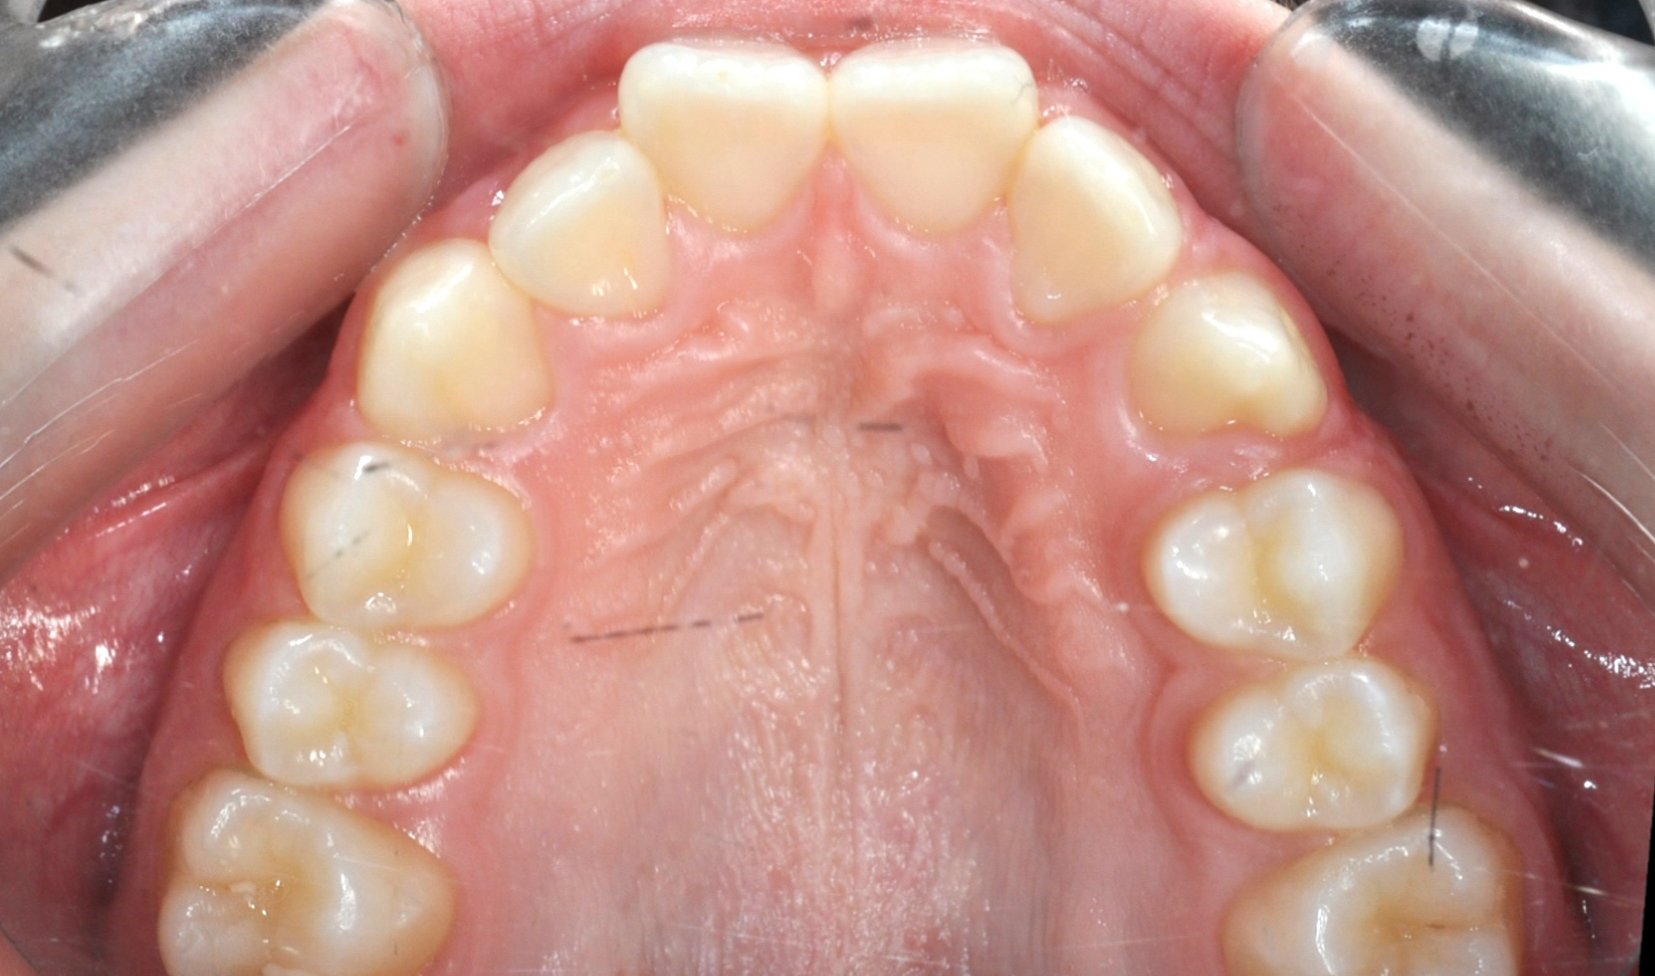

Caso 2 – Allineatori trasparenti in paziente adulto

Paziente adulto con importante affollamento dei denti inferiori, arcate strette e tendenza al morso aperto, con difficoltà nel corretto contatto tra i denti superiori e inferiori.

Il trattamento con allineatori trasparenti ha permesso, in circa 18–20 mesi, di riallineare i denti, ampliare le arcate e migliorare la chiusura del morso, ottenendo un risultato stabile, funzionale ed esteticamente armonioso.

DOPO